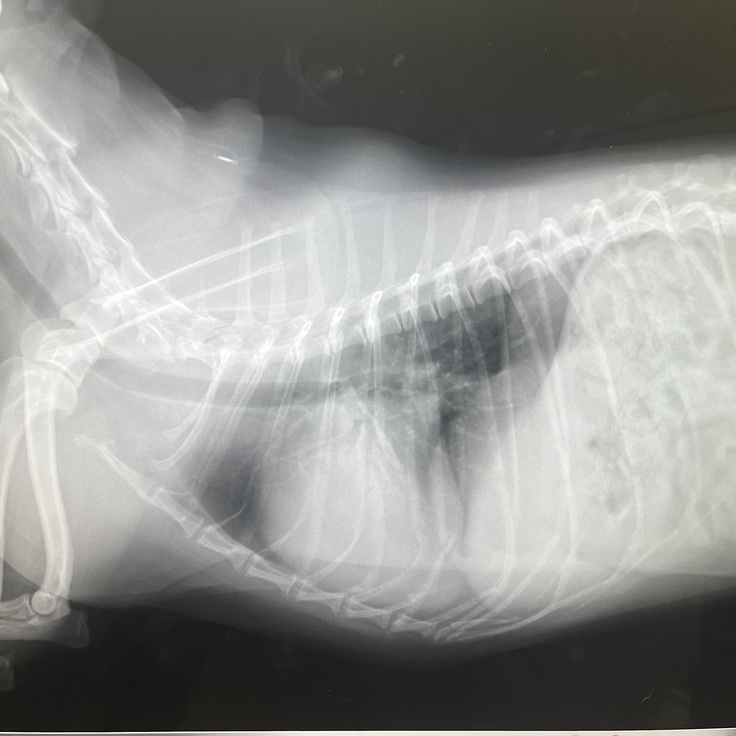

現在のレディの心臓の状態です

健康の犬の心臓に比べパンパンに

膨れ上がった心臓です。

緊急入院した時先生に心臓肥大が酷い、そのせいで気道も圧迫され呼吸数もできずそれに加え肺水腫になっているので相当苦しいはず、